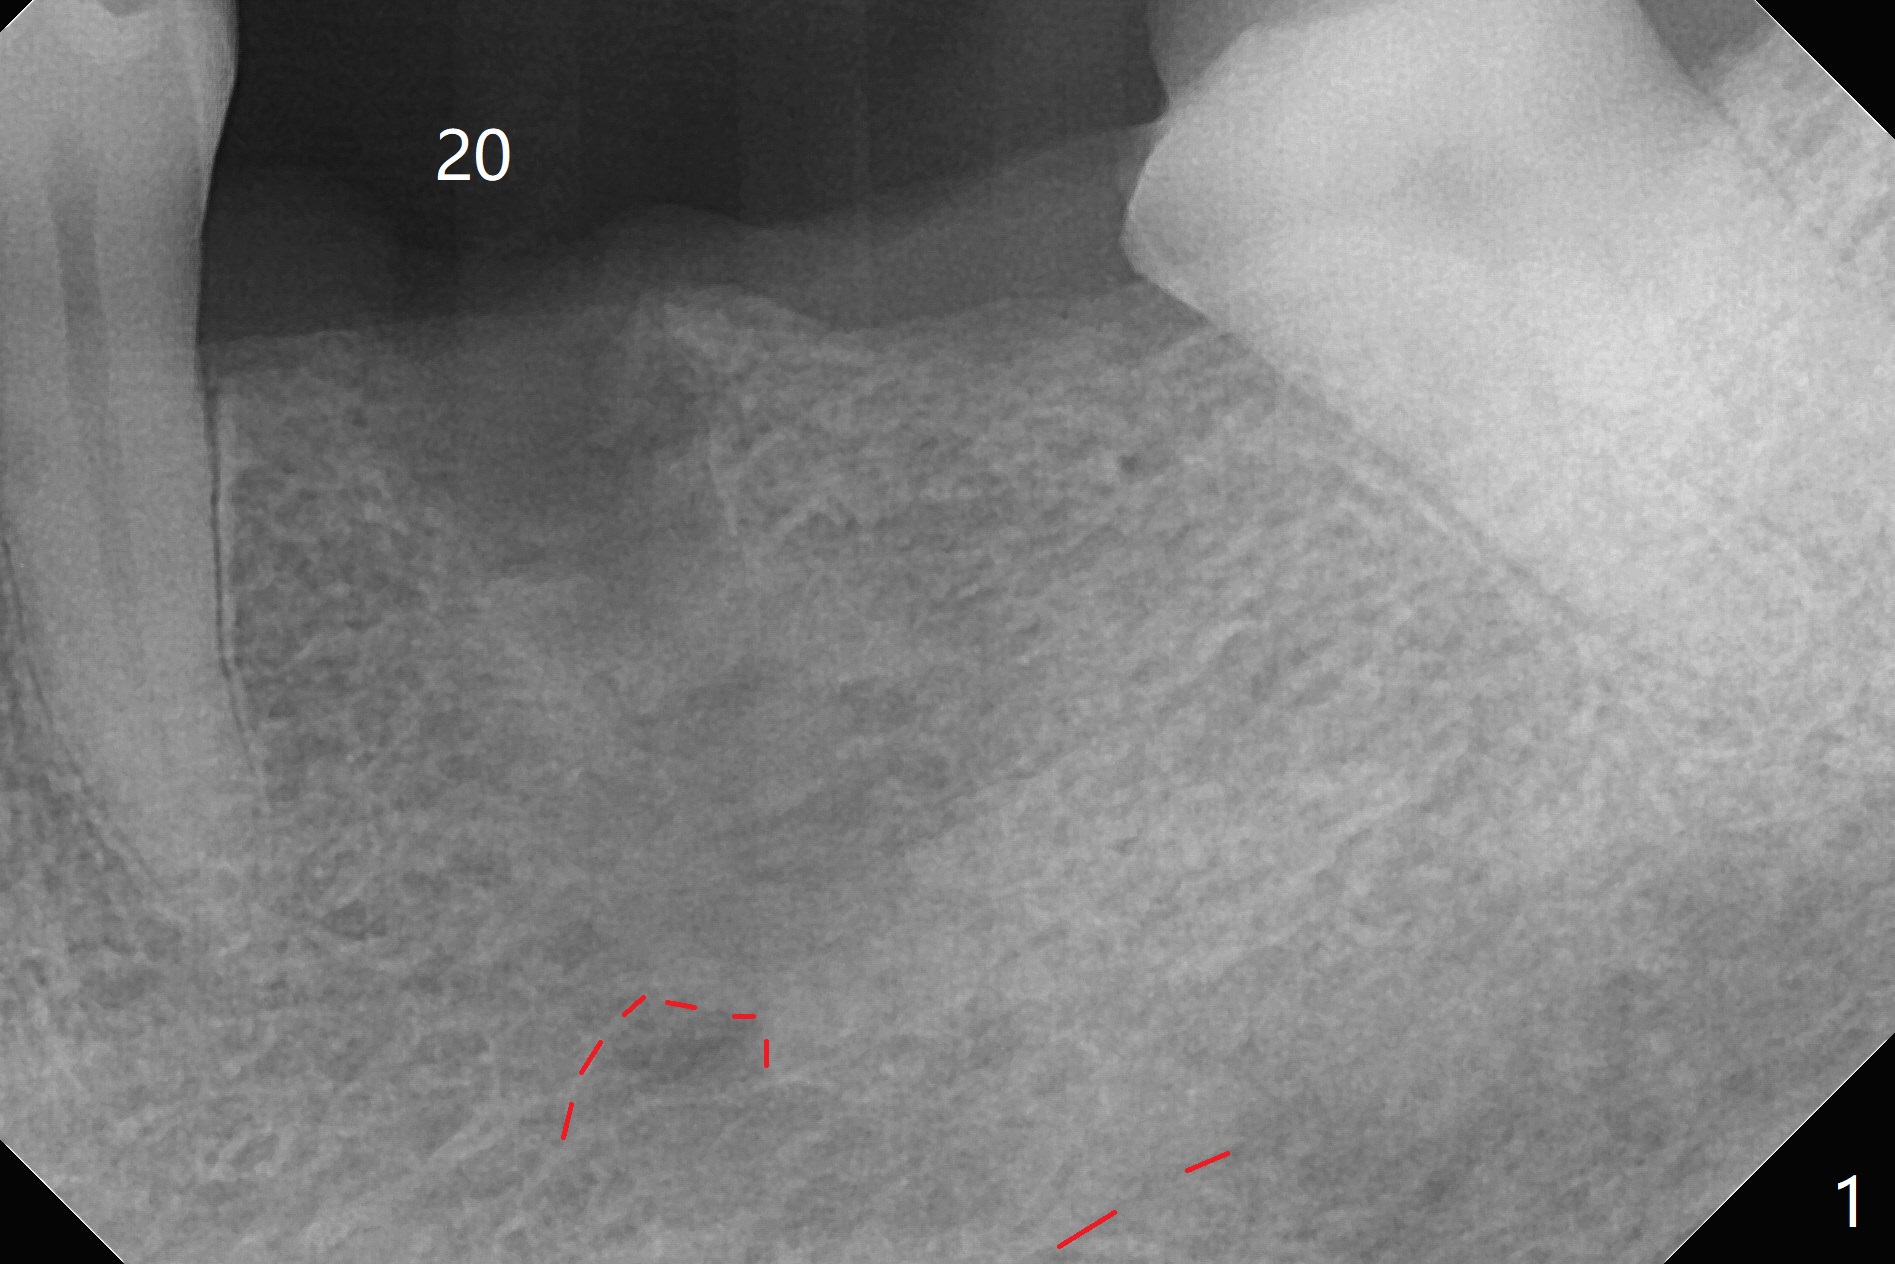

When the tooth #20 is extracted, the buccal and lingual plates are intact, but the apical lesion is deep. A PA is taken (Fig.1). Osteotomy will be established either along the long axis of the original socket (Fig.2 a line) or in the mesial slope (b line). Either osteotomy may damage the Mental Loop (red dashed line). To reduce the complication, osteotomy is being made by inserting 3.8 to 6 mm taps. In fact the 6 mm tap achieves stability (Fig.3,4), but it invades the buccal gap. When the tap is removed, the bottom of the socket is sensitive to probing with oozing from the socket. To reduce further compromise of the buccal space, Lindamann bur is used to remove the bone from the lingual and mesial plate, followed by placing a 6x17 mm implant with >50 Ncm (Fig.5). In fact the implant is placed shallower than the tap. When a 4x17 mm implant is placed at #19, there seems to be clearance from the Inferior Alveolar Canal (Fig.6). Postop there is no paresthesia. The buccal gap is <1 mm, which is filled with Vanilla Graft. After recementing the retainer (crown, C in Fig.7) at #18, periodontal dressing is applied to the sites of #19 and 20. Impression is taken 4 months postop with that of #15.